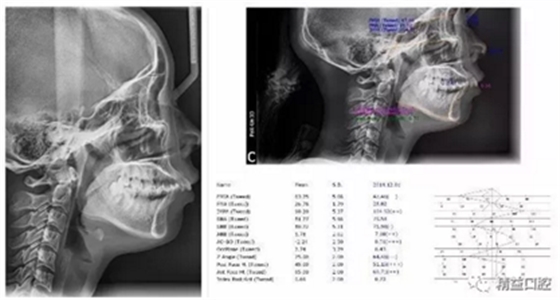

矯正前全口曲斷片

從片子上可以清除看到,上牙門牙牙根吸收非常厲害。

矯正前頭顱側(cè)位片

嘴唇突度非常明顯,后期經(jīng)過測量,發(fā)現(xiàn)是典型的安氏II類加骨性II類,齙牙前突。